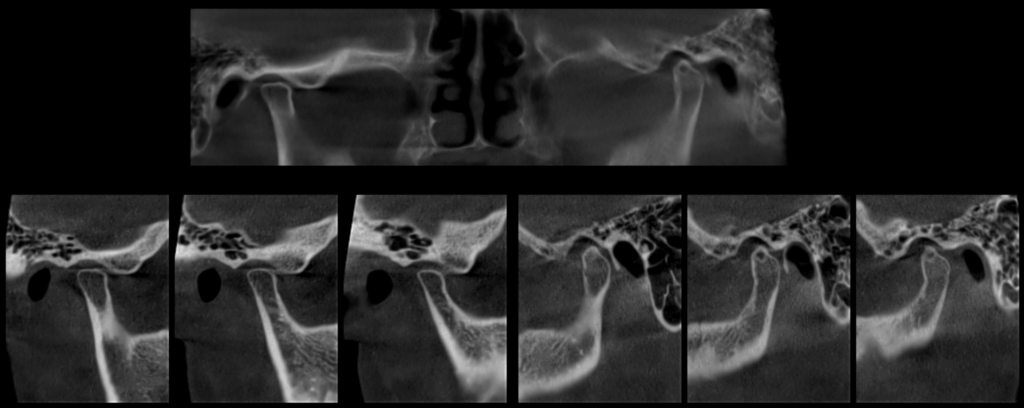

En la reformación panorámica (Figura 1), se aprecia aplanamiento de los contornos de los cóndilos mandibulares, además se observa imagen radiolúcida unilocular proyectada sobre cóndilo mandibular izquierdo, de limites definido, bordes corticalizados.

Radiografia Panorámica

A la evaluación de la tomografía volumétrica (CBCT) de la ATM en boca cerrada, en los cortes axiales (Figura 2), coronales (Figura 3) y sagitales (Figura 4), se aprecia aplanamiento de la vertiente posterior del cóndilo mandibular del lado izquierdo con presencia de imagen hipodensa localizado próximo a la vertiente superior compatible con quiste subcondral, además se aprecia disminución de espacio articular posterior en ATM izquierda y disminución del espacio articular anterior en ATM derecha.